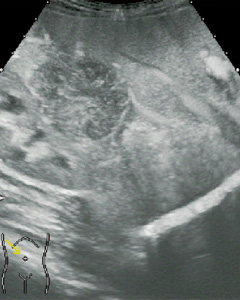

■ Flash機能とMicrobubble Trace Imaging(MTI)(図3)

体内に貯まったソナゾイドは,高音圧送信することで破壊することができる。

Flash機能は高音圧送信でソナゾイドを破壊し,再環流を観察する機能である。また,MTIは,造影剤による高輝度部を重ね合わせる画像で,血管像の観察に適している。

図3 HCCのMTI像 (画像ご提供:三重大学 田中秀明先生)

b:LowMIでのFundamental像